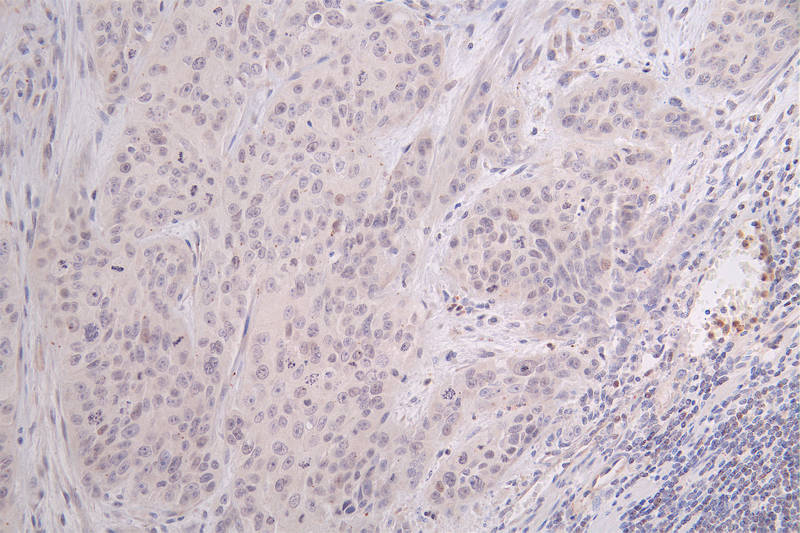

IHC image of CSB-RA148519A0HU diluted at 1:100 and staining in paraffin-embedded human breast cancer performed on a Leica BondTM system. After dewaxing and hydration, antigen retrieval was mediated by high pressure in a citrate buffer (pH 6.0). Section was blocked with 10% normal goat serum 30min at RT. Then primary antibody (1% BSA) was incubated at 4°C overnight. The primary is detected by a Goat anti-rabbit polymer IgG labeled by HRP and visualized using 0.09% DAB.

IHC image of CSB-RA148519A0HU diluted at 1:100 and staining in paraffin-embedded human gastric cancer performed on a Leica BondTM system. After dewaxing and hydration, antigen retrieval was mediated by high pressure in a citrate buffer (pH 6.0). Section was blocked with 10% normal goat serum 30min at RT. Then primary antibody (1% BSA) was incubated at 4°C overnight. The primary is detected by a Goat anti-rabbit polymer IgG labeled by HRP and visualized using 0.09% DAB.